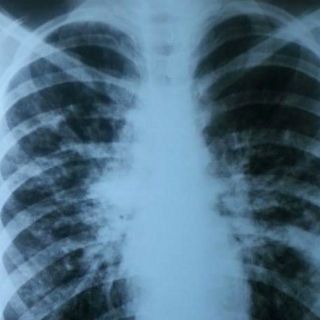

CIUDAD DE MÉXICO (26/MAR/2016).- Tos crónica, falta de aire al realizar actividad física, sinusitis y deshidratación, son algunos de los síntomas que indican la presencia de fibrosis quística (FQ) en los niños.

En ese sentido, expuso que "es importante estar atento a otro tipo de síntomas como dolor abdominal por estreñimiento grave, aumento de gases o abdomen que parece distendido, náuseas o falta de apetito, heces pálidas, fétidas y con moco, y pérdida de peso".